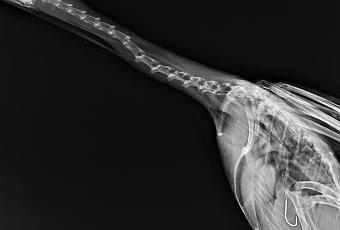

El cormorán del que podéis ver su radiografía fue recogido en la playa de Bañugues en agosto de este año mientras luchaba por soltarse de un palangre. Se lo había tragado pensando que era un pez inofensivo, quizás demasiado fácil de capturar. Mientras subía la marea, ya con el anzuelo clavado en el estómago, se le hacía cada vez más difícil mantenerse en la superficie para poder respirar. Y a cada intento de soltarse, el anzuelo se clavaba más y más profundo mientras iba desgarrándolo por dentro.

Afortunadamente pudo ser rescatado antes de morir ahogado, pero el anzuelo se le había clavado tan profundo que los veterinarios no fueron capaces de sacárselo por temor a producirle más lesiones que las que ya tenía. Se tuvieron que limitar a cortar el sedal lo más abajo posible y a confiar en que se pudiera recuperar.